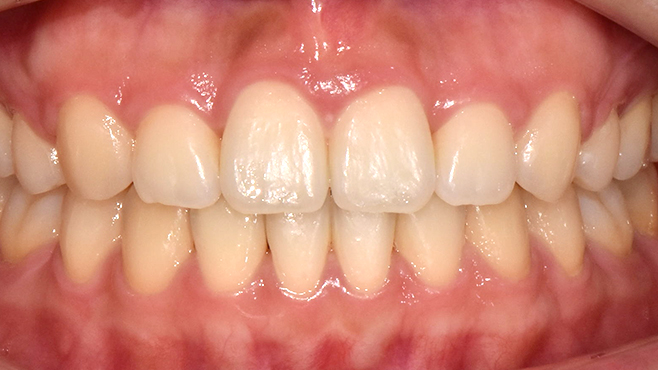

before

after

※ 위 임상사진은 동일조건으로 촬영되었으며, 사진에 대한 별도의 조작이 처리되지 않았습니다.

※ 위 임상사진 및 포트레이트는 환자와의 포괄적인 초상권 계약 이후 사용하고 있습니다.

※ 수술 및 치료과정에서 부작용이 발생할 수 있으므로 충분한 상담과 신중한 판단이 요구됩니다.

실제 치료 사례

수많은 환자들이 고민 끝에 선택한 치료,

그리고 그 후의 놀라운 변화

- ※ 위 임상사진은 365서울원탑치과에서 진료를 시작하고 마친 동일한 환자의 사진입니다.

- ※ 위 임상사진은 동일한 장소에서 동일한 조건으로 촬영되었으며, 사진에 대한 별도의 조작이 처리되지 않았습니다.

- ※ 수술 및 치료 과정에서 부작용이 발생할 수 있으므로 의료진과의 충분한 상담과 신중한 판단이 요구됩니다.